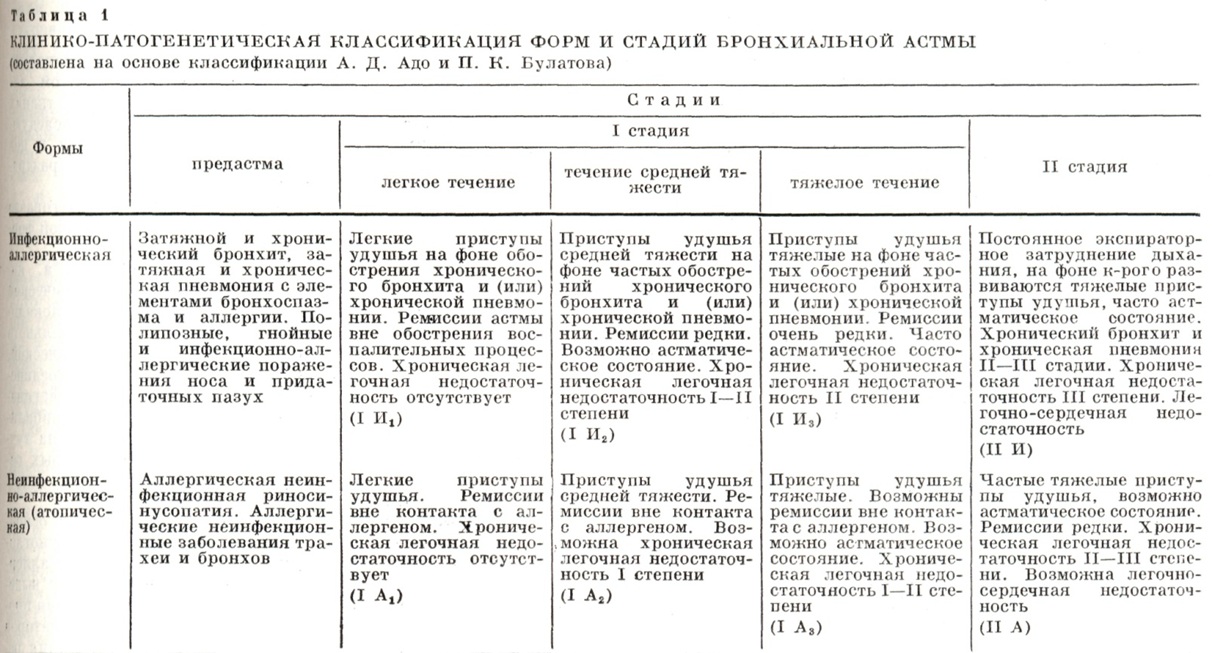

При микроскопическом исследовании (цветн. рис. 5 и 6) видно, как в просвете бронхов и бронхиол слизь образует концентрические слои.

В ней много эозинофилов, клеток и целых пластов слущенного эпителия. Слизистая оболочка бронхов отёчна, рыхло инфильтрирована лимфоидными, плазматическими клетками и эозинофилами. В субсегментарных и меньших бронхах слизистая оболочка как бы гофрирована с полиповидными выбуханиями, в к-рых располагаются мышечные пучки. Стенки мелких бронхов и бронхиол густо инфильтрированы эозинофилами, распространяющимися на прилежащие альвеолярные перегородки. Базальная мембрана утолщена, гомогенизирована. В эпителии явления гиперсекреции и десквамации. Бокаловидные клетки эпителия, просветы слизистых желез и расширенные выводные протоки заполнены секретом, имеющим ШИК-положительную реакцию. Мышечные пучки отёчны. В лёгочной ткани — явления эмфиземы, альвеолы и входы в них расширены, встречаются очаги ателектаза и эозинофильной пневмонии. Наблюдается расширение и полнокровие сосудов стенок бронхов и легочной ткани, расширение просветов артерио-венозных анастомозов, иногда сужение сосудов, что свидетельствует о функциональных изменениях не только бронхов, но и сосудов и расстройствах кровообращения, усиливающих кислородную недостаточность.

При иммунологических исследованиях, проведённых в последние годы американскими учёными, установлена локализация иммуноглобулина Е на базальных мембранах, в клетках эпителия и слизистых железах (преимущественно мелких бронхов) как во время приступа, так и нек-рое время после него.

Предполагают, что на базальной мембране происходит взаимодействие иммуноглобулина Е с антигеном.